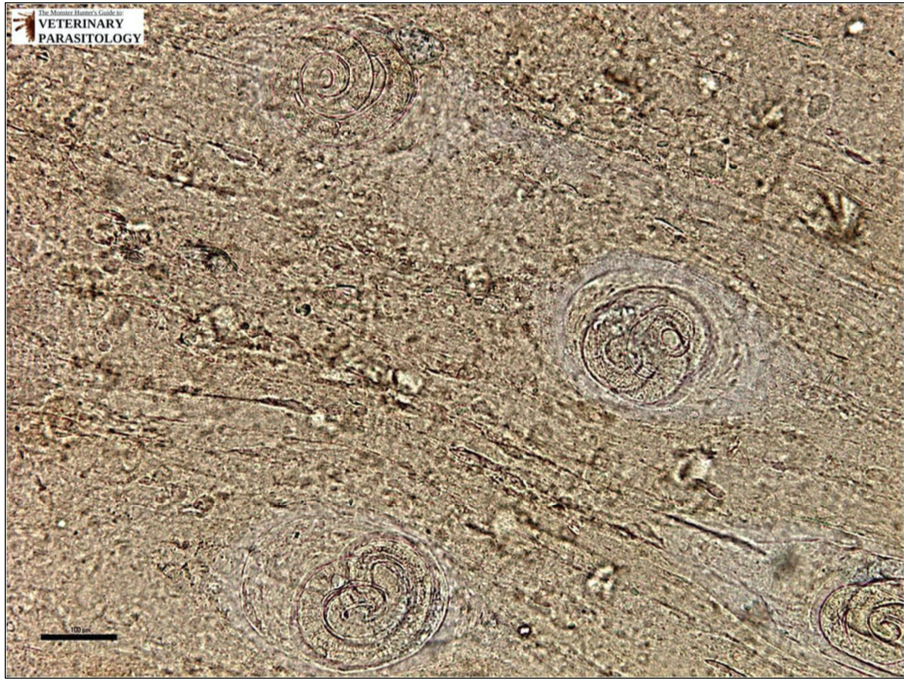

Trichinella: L1 dans le muscle